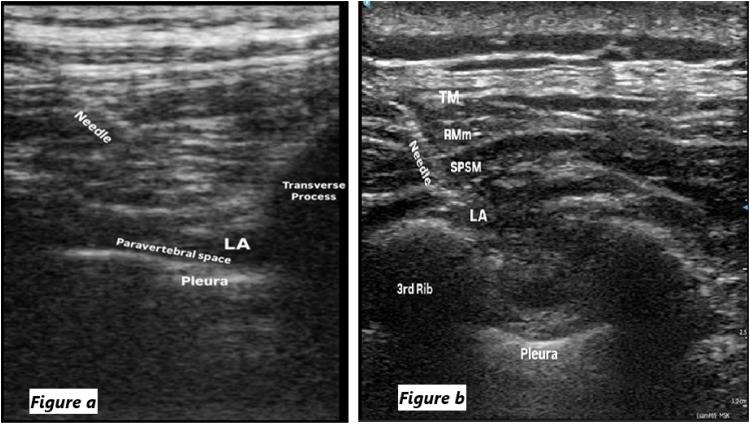

Video-Assisted Thoracoscopic Surgery (VATS) is a minimally invasive procedure associated with faster recovery and fewer complications compared to open thoracotomy. Effective postoperative pain management is important for optimizing recovery. This study compares the analgesic efficacy of the Serratus Posterior Superior Intercostal Plane Block (SPSIPB) and Thoracic Paravertebral Block (TPVB) for postoperative pain following VATS.

与开胸手术相比,电视辅助胸腔镜手术(VATS)是一种微创手术,恢复更快,并发症更少。有效的术后疼痛管理对于优化恢复很重要。本研究比较了后上锯肌肋间平面阻滞(SPSIPB)和胸椎旁神经阻滞(TPVB)对VATS术后疼痛的镇痛效果。